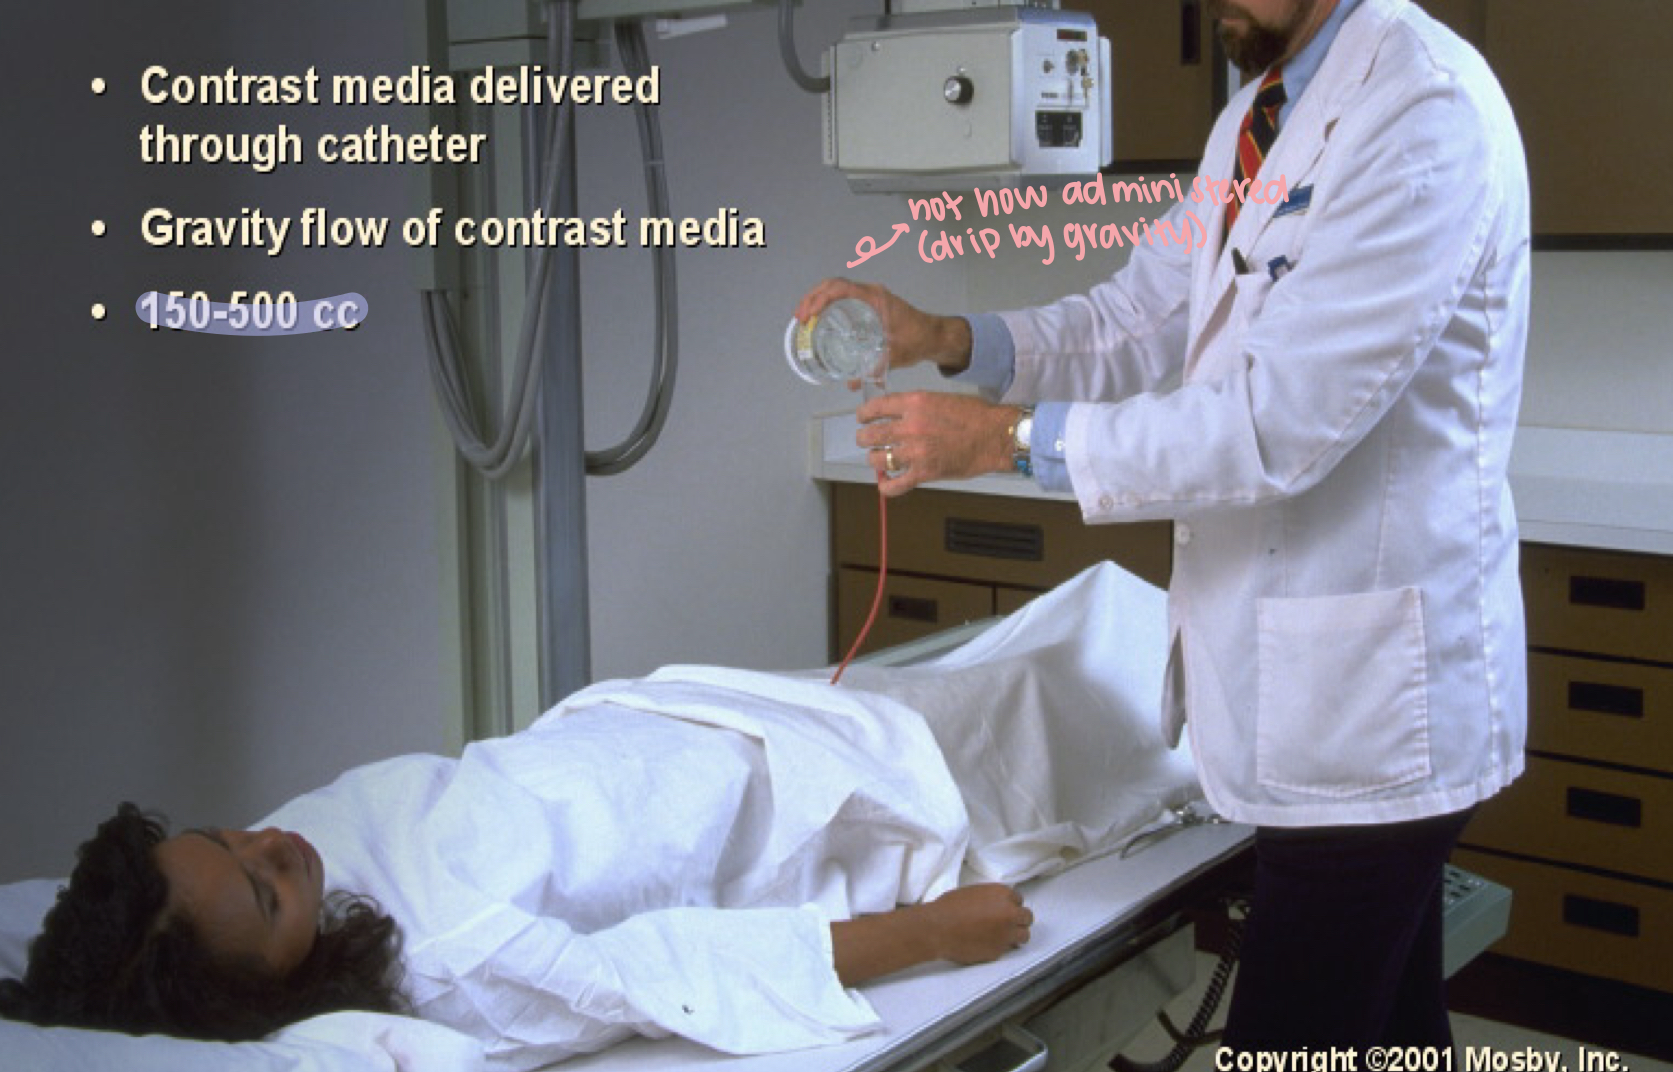

What position is this?

Retrograde urography

What is this demonstrating?

Retrograde cystography